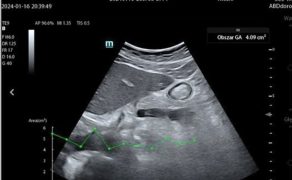

Kolejnym krokiem jest automatyczna identyfikacja struktur anatomicznych oraz wykonywanie złożonych pomiarów, które dotychczas wymagały wysokiej biegłości technicznej. W praktyce klinicznej obejmuje to m.in. automatyczną ocenę funkcji skurczowej serca, analizę przepływów, ocenę zmienności wymiarów naczyń czy identyfikację charakterystycznych artefaktów płucnych. Z punktu widzenia anestezjologii i intensywnej terapii kluczowe znaczenie ma fakt, że pomiary te wykonywane są szybko, powtarzalnie i w sposób ustandaryzowany, co znacząco ogranicza zmienność między operatorami i poprawia bezpieczeństwo podejmowanych decyzji (4).

Najistotniejsza zmiana zachodzi jednak na poziomie interpretacji danych. Tradycyjnie ultrasonografia była narzędziem opisowym, a lekarz samodzielnie formułował hipotezy diagnostyczne na podstawie obserwowanego obrazu. Współczesne systemy AI przesuwają ten proces w kierunku interpretacji wspomaganej algorytmicznie, w której obraz ultrasonograficzny integrowany jest z innymi danymi klinicznymi i prezentowany w postaci sugestii diagnostycznych, trendów lub wskaźników istotnych klinicznie. Sztuczna inteligencja porządkuje dane i zmniejsza obciążenie poznawcze lekarza, nie przejmując jednak odpowiedzialności za decyzję (2, 3, 7).